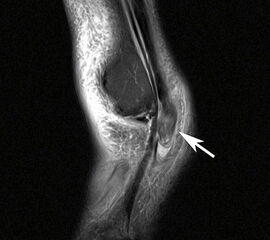

Unterbrechung des Retinakulums als indirektes Zeichen einer traumatischen Peronealsehnenluxation im MRT.

Abbildung 6

Neben der klinischen Untersuchung besitzt in der Diagnostik von Sehnenpathologie das MRT mit Kontrastmittel einen hohen Stellenwert 8910. Kontrastmittelaufnahme in die Sehne ist immer als Hinweis auf einen Riss zu werten. Weiterhin ist Flüssigkeit im Sehnengleitlager oder die Aufnahme von Kontrastmittel in das Sehnengleitgewebe ein indirektes Zeichen einer Sehnenpathologie.